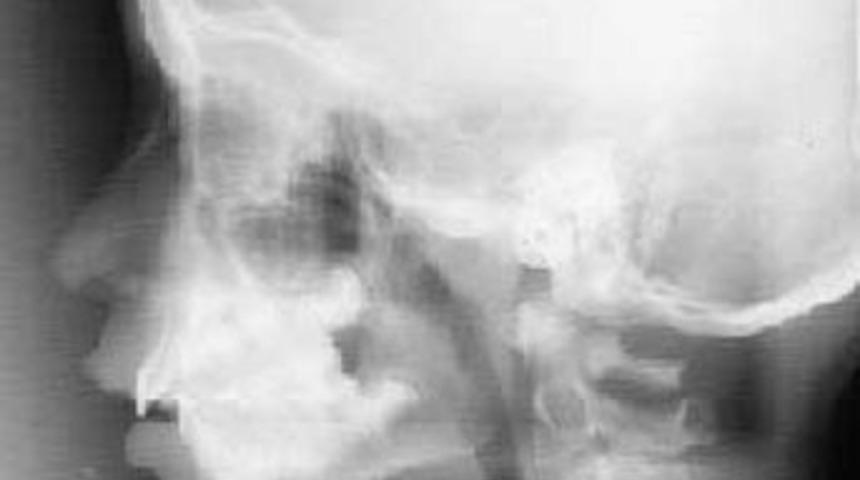

Şiddetli baş ağrılarıyla doktora başvuran kadın inanılmaz bir gerçekle karşılaştı. Kadının elmacık kemiğinde 12 yıl önce saplanmış bir kurşun bulundu.

ATA haber ajnasının haberine göre; Mrike Rrucaj adlı kadın 12 yıl boyunca elmacık kemiğinin altına isabet eden bir kurşunla yaşadı.Olayı nasıl gerçekleştiğini bilmediğini anlatan kadın, sürekli bir baş ağrısı yaşadığını ve bu nedenle doktorra gittiğinde bu gerçekle karşılaştığını söyledi.

1997 yılında Arnavutluk'taki evinin kurşunlandığı anlatan Mrike Rrucaj, "Uyandığım zaman her tarafım kanla kaplanmıştı. Ve kocam beni acil servise götürmüştü. Beni tadevi eden doktorlar, bana kurşunun çıkarıldığını ve yarayı temizlediklerini söylemişlerdi" dedi.Bu olaydan sonra sürekli bir baş ağrısı çektiğini ifade eden talihsiz kadın, "Daha sonra çekilen röntgenlerimde kurşunun halen çenemde durduğu gördüm" şeklinde konuştu.